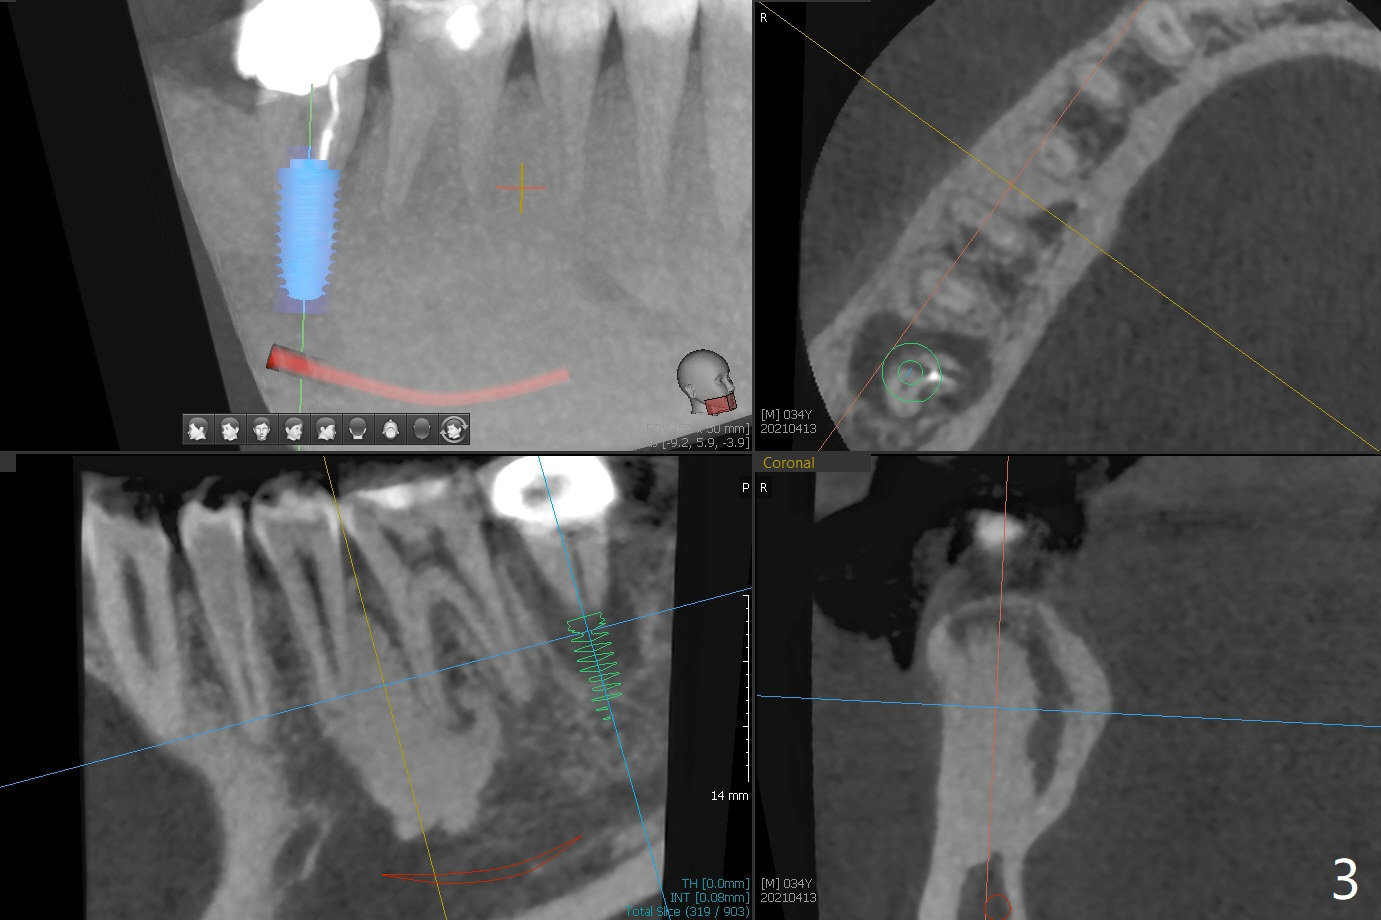

34岁男抱怨右下7根管治疗后牙齿松动,根尖片证实根裂(图一),第二前磨牙和第一磨牙之间有致密骨质(图一:*,图三)。尽管患牙周围骨质吸收严重,尤其是颊侧牙槽嵴(图二:B),必须做即刻种植。植骨有时效果不佳,没有减少手术难度。拖延治疗可能增加对合牙过度萌出,尤其是咬合力大病人。虽然植体颊侧螺纹有暴露危险(图四:>),但是颊侧牙龈附着很长(双箭头),结合基台(图五:粉红色)和临时牙冠(白色),牙龈创造有利的植骨床(红色:骨粉)。